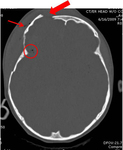

Axial CT scan showing nondepressed linear skull fracture (arrow) of the skull base involving the foramen magnum. This injury pattern is concerning for associated spinal fracture, cord injury, and blunt cerebrovascular injury

From the teaching collection of Demetrios Demetriades; used with permission